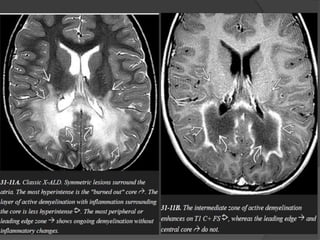

A posterior-predominant pattern is seen in 80% of patients with X-

ALD.

The earliest finding is T2/FLAIR hyperintensity in the middle of

the corpus callosum splenium.

As the disease progresses, hyperintensity spreads from posterior

to anterior and from the center to the periphery.

The peritrigonal WM, corticospinal tracts, fornix, commissural

fibers, plus the visual and auditory pathways can all eventually

become involved.

The leading edge of demyelination appears hyperintense on

T1WI but does not enhance.

The intermediate zone of active inflammatory demyelination

often enhances on T1 C+.

Diffusion restriction in the intermediate zone of inflammatory

demyelination may be present on DWI.

MRS shows decreased NAA even in normal-appearing WM.

Elevated choline, myoinositol, and lactate are common.